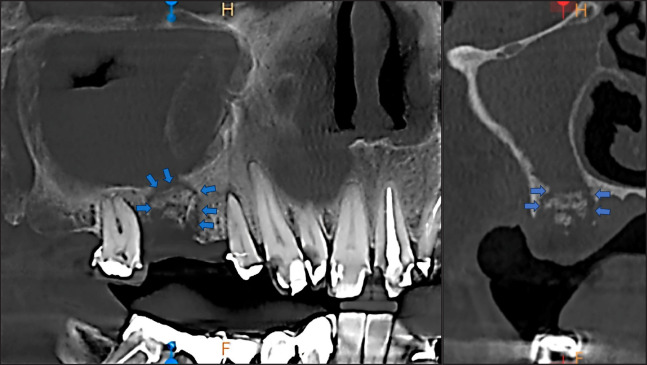

Methods: A female patient, 62 years old, was referred to the Department of Dentoalveolar Surgery, Surgical Implantology and Radiology, School of Dentistry, Aristotle University of Thessaloniki, Greece, complaining about pain in the first quadrant. Her medical history revealed per os bisphosphonate administration for the past four years. Subsequently, the cone-beam computed tomography examination revealed a small sequestrum of bone, surrounded by radiolucency, in proximity with the sinus floor. The clinical examination didn't reveal any pathological clinical signs.

Results: Based on the radiological examination, a surgical approach was implemented to remove the necrotic bone, irrigate the alveolar process and the sinus with saline, and finally achieve primary closure, after which, the patient healed uneventfully. The osteonecrosis was attributed to the bisphosphonate administration.